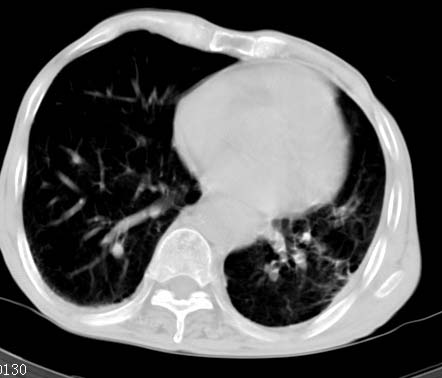

男性病人 81岁 胸痛 咳嗽2月 2周前提示右下肺感染.

今片ct示双肺多发结节影 可以这样诊断吗?1\双肺感染性病变 结核待排.

2\双肺纤维硬结灶,左肺肺气肿.

3\肺间质纤维化,胸膜肥厚粘连.

纵隔左移双肺上叶纤维硬结,肺气肿,双侧斑痕肺大泡,双侧胸膜增厚并胸膜下陈旧性病灶,右肺下叶胸膜下小结节影,密度较淡,建议复查.

此病人,诊断如下:1、双肺陈旧结核,活动与否请结合临床及其它检查。2、慢支炎,肺气肿,并双肺

多发肺大泡。3,胸膜肥厚、粘连。4、右下肺多个小结节,转移瘤不能除外。

病人桶状胸,胸廓肌肉消瘦;两上肺均可见纤维条索灶,下肺外围胸膜下可见间质纤维化改变,右下肺沿肺纹理分部结节样病灶,边缘光滑,考虑1、慢支并局灶性间质纤维化、右下肺合并感染,2、两上肺为陈旧性肺结核灶并瘢痕旁型肺气肿3、右下肺转移瘤待排。

两肺上叶见多发索条状高密度影,右肺下叶见片状、结节状高密度影,两肺体积增大,胸膜下区见囊状低密度影、内有分隔结构。左肺下叶见网格影。两侧胸膜见增厚影。诊断:两肺继发性肺结核。慢性支气管炎合并感染。肺气肿。肺间质纤维化。胸膜增厚。